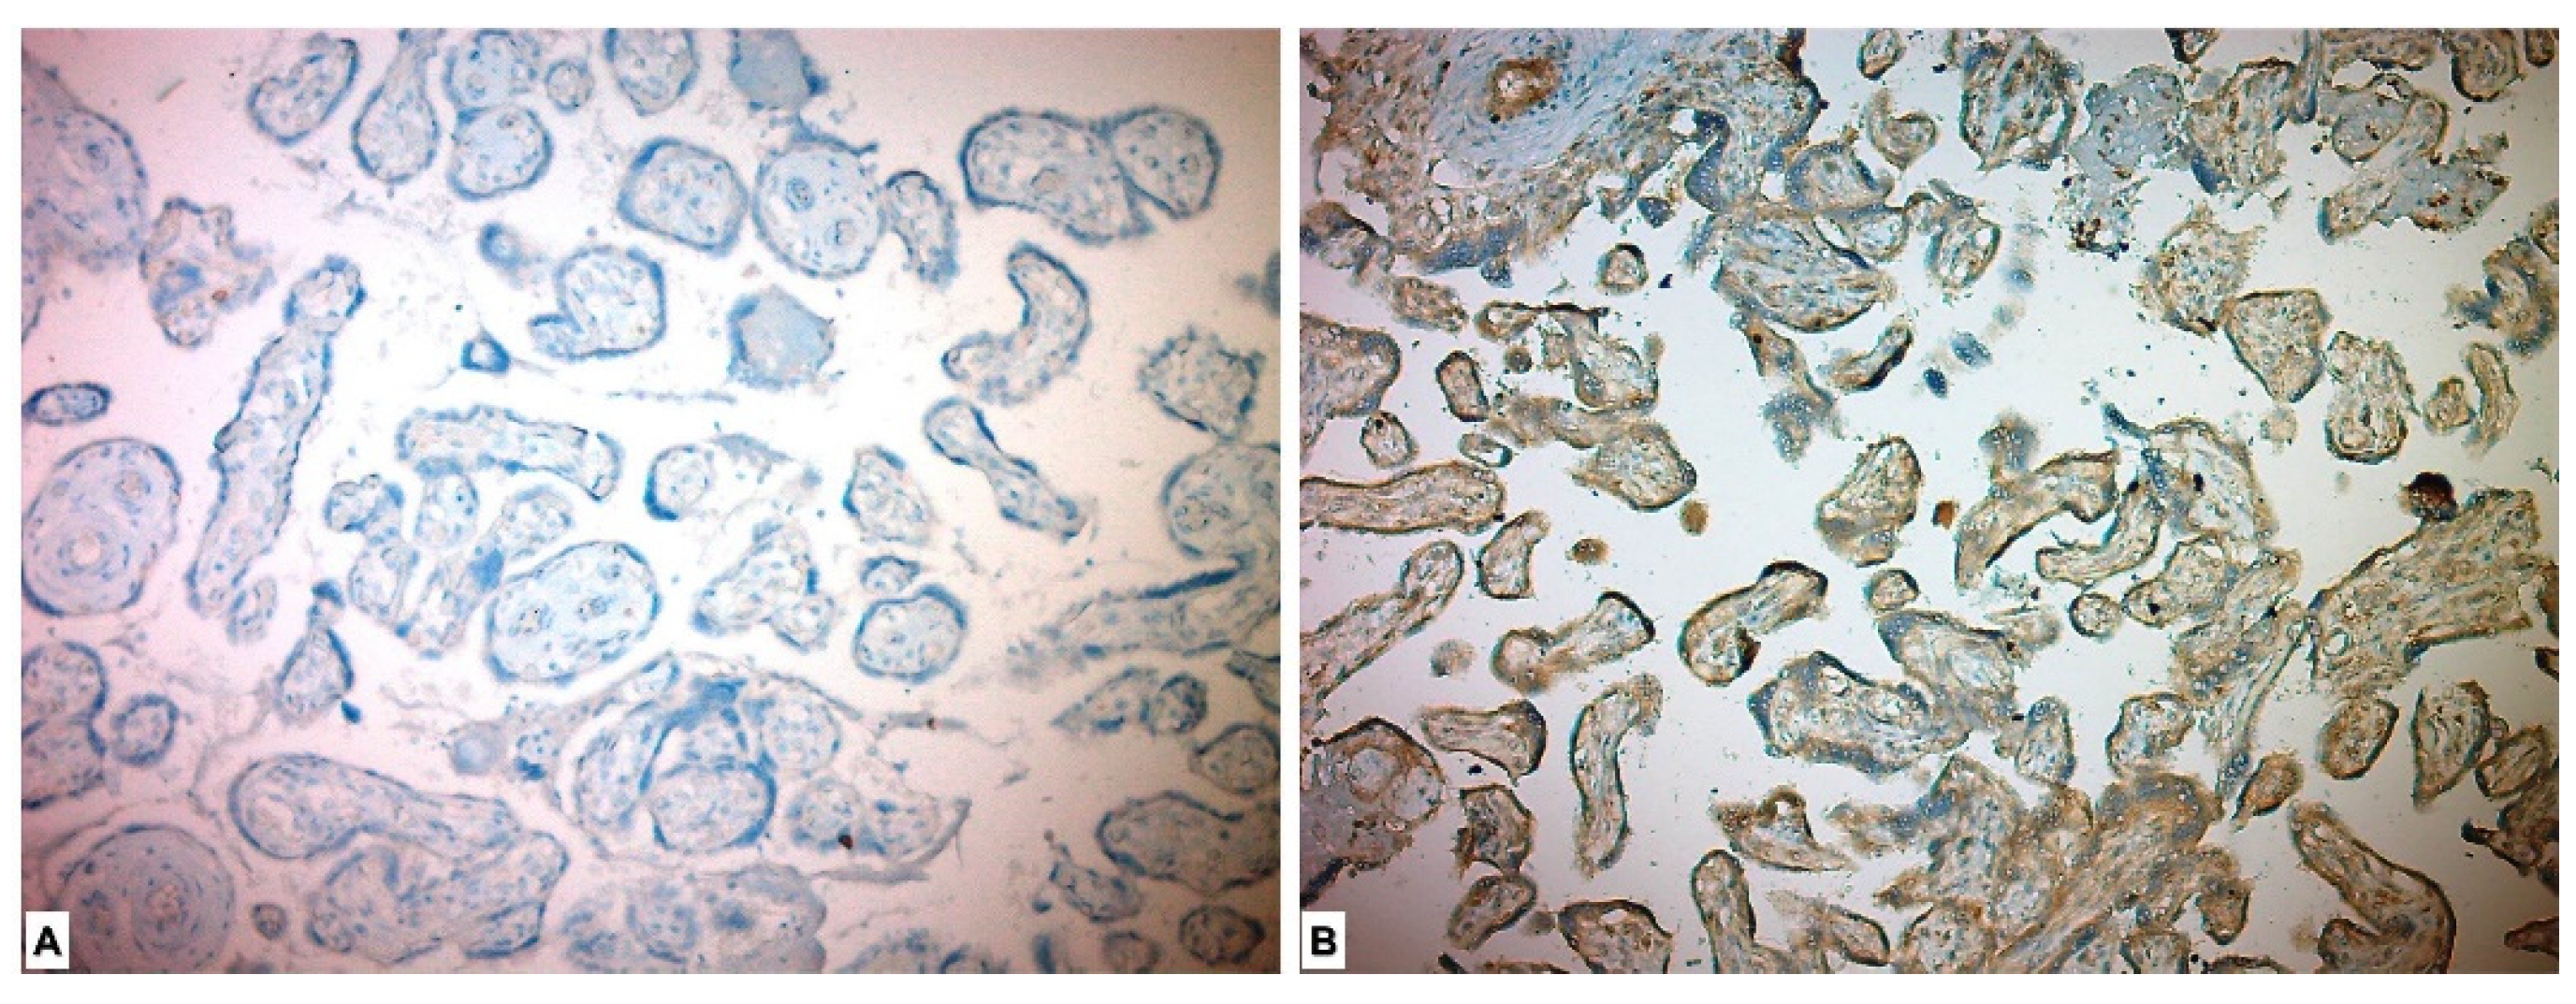

Immunohistochemical evaluation could not be performed for four of the placentas due to alack of appropriate staining. In the immunohistochemical study performed for the CD56 Ab, 27 (48.2%) of the study group placentas showed low expression and 29 (51.8%) showed high expression. Forty-three (100%) in the control group placentas showed low expression. When compared with the chi-square test, the placentas in the study (PE) group were more stained with CD56 marker, and the difference between the two groups was found to be significant (p < 0.001) (Table 3, Figure 2).

Figure 2.

Immunohistochemical expression of CD56 in placental tissues. (A) Low CD56 expression in control group placenta. (B) High CD56 expression in preeclamptic placenta, more intense in syncytiotrophoblast and cytotrophoblast.